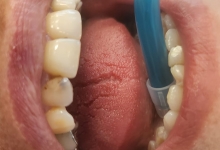

– izolare cu diga